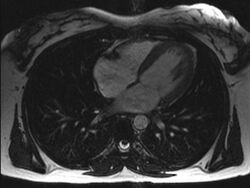

An MRI of a 13 year old female's heart beating.

Axial MRI image at the level of the heart

Magnetic resonance imaging visualizes the heart by detecting hydrogen atoms using superconducting magnets, particularly those attached to water and fat molecules.[9] These hydrogen atoms possess a property known as nuclear spin. Although the direction of this spin is usually random, the spin can be aligned using a powerful magnetic field.[9] Faint electromagnetic signals are emitted by these hydrogen atoms when their alignment is temporarily disturbed which can be detected and used to create an image of the heart.[10]